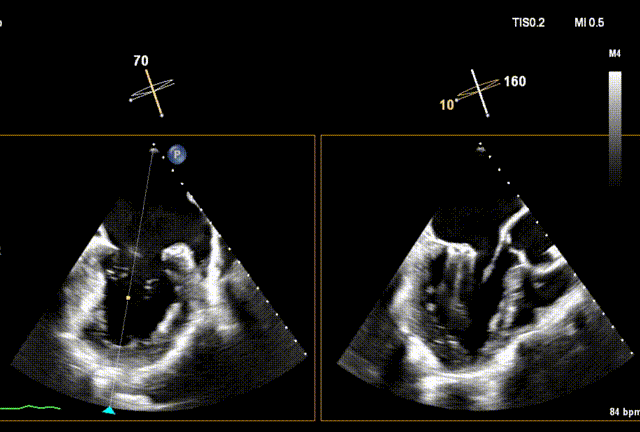

手术回顾

下夹撤入心室

上下夹搭合

3D再次确认位置及钟向

收入闭合环

解离释放

术后3D动图

夹合后二尖瓣反流量0+,平均跨瓣压差3mmHg